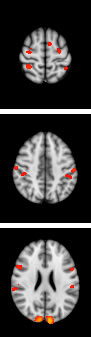

These fMRI images show my brain activity during a combined sensory task involving finger tapping and viewing a flashing checkerboard.